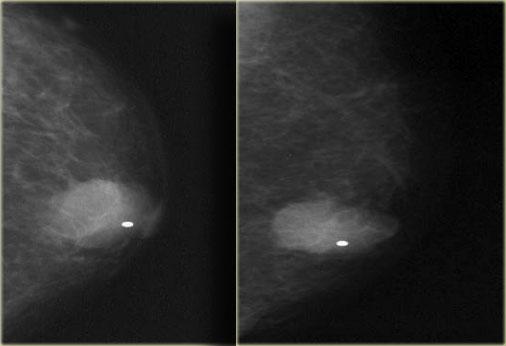

Bên trái là một trường hợp u cơ xơ bào khác.

Tổn thương biểu hiện là một khối có múi, bờ rõ, không có vôi hóa.

Lưu ý rằng tổn thương nằm lệch tâm so với núm vú.

Khối có múi này mới cần được sinh thiết, không phải tổn thương vú to nam giới vùng sau núm vú.

Núm vú được đánh dấu và tổn thương không nằm ở vùng sau núm vú.

Trên hình ảnh siêu âm, tổn thương khó phân biệt với mô mỡ xung quanh.